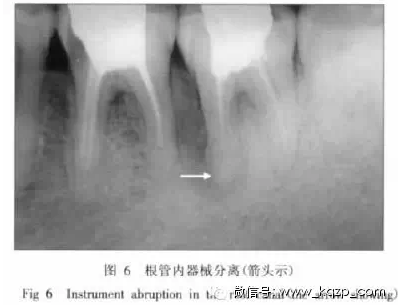

3.5 根管內(nèi)器械分離

在根管預(yù)備過程中,無論使用不銹鋼根管銼,還是鎳鈦根管銼,都會發(fā)生器械在根管內(nèi)分離的情況。Iqbal等[8]發(fā)現(xiàn),磨牙發(fā)生器械分離的幾率是前磨牙的2.9倍;根尖1/3處發(fā)生斷針的幾率是根管冠方及根中1/3處的6倍。但是,斷針在牙片上表現(xiàn)出來的阻射情況,有時和根管充填物密度非常接近,特別是當(dāng)斷針和根管充填物連接在一起時,兩者更難分清,這就需要進(jìn)一步觀察根管充填的密合度和根管邊緣的自然彎曲情況(圖6)。